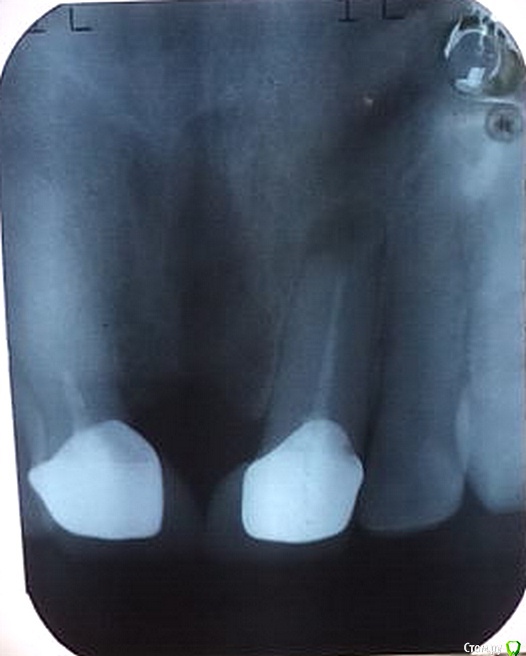

ARislanV Опубликовано 19 марта, 2015 Поделиться Опубликовано 19 марта, 2015 Пациентка 50 лет, в 2010 году была произведена резекция 21 зуба с последующей установкой коронки. Жалобы: на редкую боль при надавливании на десну в области корня 21 зуба. Объективно: Коронка в норме, зуб не подвижен, вертикальная перкуссия б/б, горизотальная слегка болезненна. Что посоветуете? Ссылка на комментарий

molchanoff Опубликовано 19 марта, 2015 Поделиться Опубликовано 19 марта, 2015 А мне кажется проблема в дизайне "промывного" пространства, тот огромный черный ромб. Ссылка на комментарий